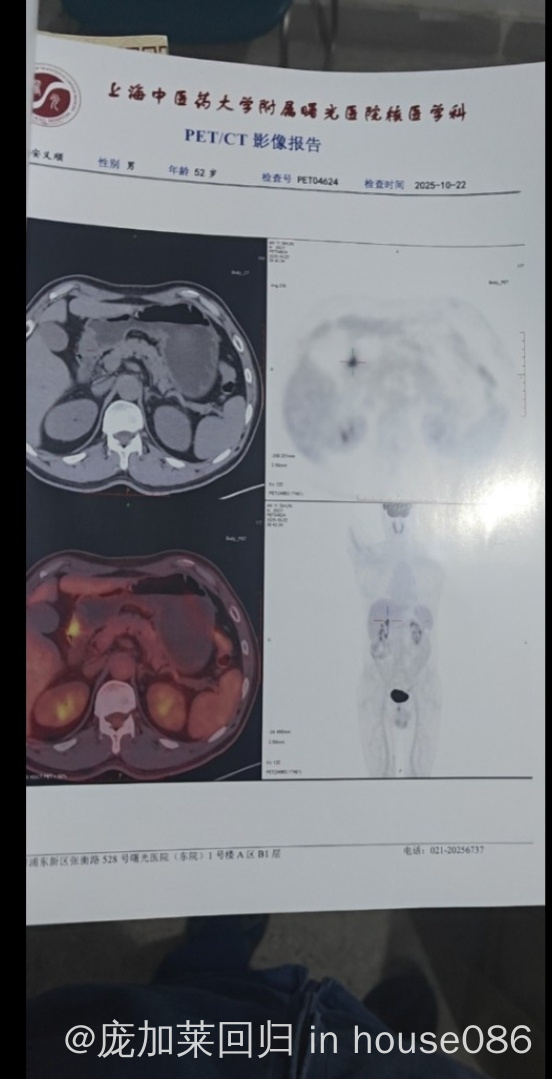

各位大佬求看我爸是淋巴癌吗 我爸没任何症状,如果是的话严重吗?求看

活检才能确诊,如果有应该也是单个病灶